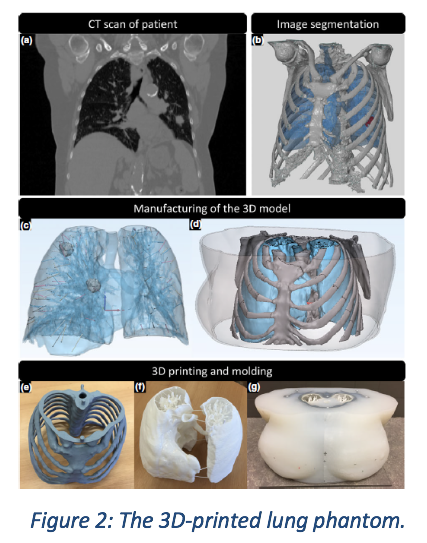

Common to both parts of MATCH are a lung phantom3, and a lung SABR planning protocol. The lung phantom is shown in Figure 2. The phantom is anthropomorphically realistic and therefore best suited to the task of evaluating markerless lung target tracking algorithms in a clinical environment. The phantom is a 3D printed anatomy taken from a real patient, including blood vessels, mediastinum with trachea and bony structures. In contrast to a real patient, the phantom can be moved with known displacements, offering a benchmark for the target position. The CT-scan and kV X-ray images of the phantom resemble closely those of a real patient. The phantom includes three targets, two of unit density and one of lower density. The lung SABR planning protocol was taken from RTOG09154, using the 12Gy per fraction arm for expediency of measurements.

Common to both parts of MATCH are a lung phantom3, and a lung SABR planning protocol. The lung phantom is shown in Figure 2. The phantom is anthropomorphically realistic and therefore best suited to the task of evaluating markerless lung target tracking algorithms in a clinical environment. The phantom is a 3D printed anatomy taken from a real patient, including blood vessels, mediastinum with trachea and bony structures. In contrast to a real patient, the phantom can be moved with known displacements, offering a benchmark for the target position. The CT-scan and kV X-ray images of the phantom resemble closely those of a real patient. The phantom includes three targets, two of unit density and one of lower density. The lung SABR planning protocol was taken from RTOG09154, using the 12Gy per fraction arm for expediency of measurements.